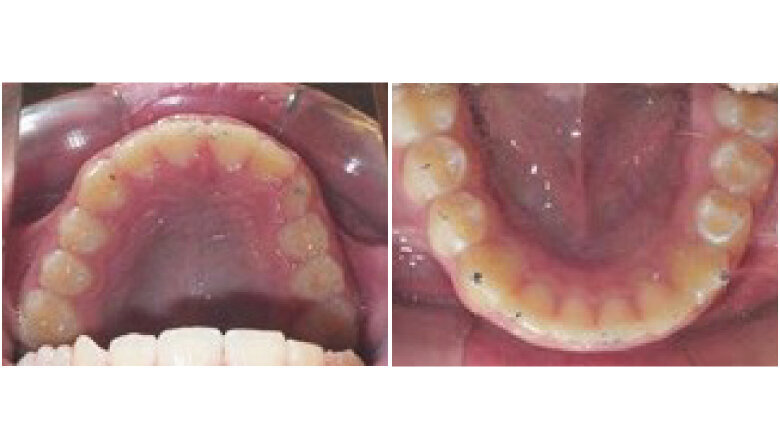

Initial Records

The patient is an 11 year 6 month old male with a chief concern of “overbite.” Diagnostic summary:

Class II, division 1 malocclusion (severe on the right, moderate on the left)

Deep overbite (moderate)

Moderate upper crowding

Mild lower crowding

The slightly retroclined upper incisors and flared lower incisors are consistent with dental compensations for a sagittal jaw discrepancy. The skeletal vertical dimension being within normal limits suggests that the deep bite is predominantly dental in nature.